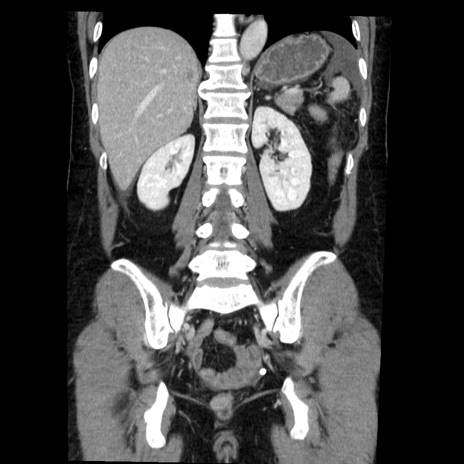

症例6(冠状断像)

【症例】50歳代女性

【既往歴】卵巣癌術後(8年前に当院で卵巣摘出)

【身体所見】 意識清明、腹部:平坦、腸蠕動音→、やや硬、下腹部自発痛・圧痛あり、反跳痛あり、筋性防御なし。

【データ】WBC 16000、CRP 0.01